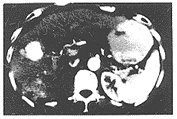

根据统计资料,动脉期15秒造影剂已到达肝内动脉,而主动脉密度150HU以下,由于造影剂浓度低,肿瘤实体强化欠佳,与邻近正常肝组织平均差值仅为6.2;而35秒,正常肝实质、肿瘤实体都显著增强,密度平均差值0.8,肿瘤边缘边界欠清,无法了解肿瘤侵犯邻近组织情况,此时已到肝实质相或门脉相早期。25秒,主动脉密度达到峰值195~230HU,在肝门区几乎可显示肝动脉肝内分支,肿瘤实体明显强化65~95HU,而正常肝组织强化不明显,对比度增加,差值最大达17.8,充分体现肝癌血管丰富,获得较纯的肝动脉相图像(见图1)。

图1 开始注射造影剂25秒后肿瘤明显强化